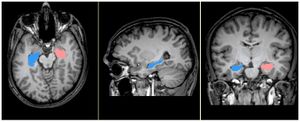

Publication: PLoS One. 2014 Jul 21;9(7):e101199. PMID: 25047083 | PDF Authors: Cavallari M, Ceccarelli A, Wang GY, Moscufo N, Hannoun S, Matulis CR, Jackson JS, Glanz BI, Bakshi R, Neema M, Guttmann CR. Institution: Dipartimento di Neuroscienze, Salute Mentale e Organi di Senso (NESMOS), Università La Sapienza, Rome, Italy. Background/Purpose: Grey matter (GM) damage is a clinically relevant feature of multiple sclerosis (MS) that has been previously assessed with diffusion tensor imaging (DTI). Fractional anisotropy (FA) of the basal ganglia and thalamus might be increased in MS patients, and correlates with disability scores. Despite the established role of the striatum and thalamus in motor control, mood and cognition, the impact of DTI changes within these structures on motor and neuropsychological performance has not yet been specifically addressed in MS. We investigated DTI metrics of deep GM nuclei and their potential association with mobility and neuropsychological function. DTI metrics from 3T MRI were assessed in the caudate, putamen, and thalamus of 30 MS patients and 10 controls. Sixteen of the patients underwent neuropsychological testing. FA of the caudate and putamen was higher in MS patients compared to controls. Caudate FA correlated with Expanded Disability Status Scale score, Ambulation Index, and severity of depressive symptomatology. Putamen and thalamus FA correlated with deficits in memory tests. In contrast, cerebral white matter (WM) lesion burden showed no significant correlation with any of the disability, mobility and psychometric parameters. Our findings support evidence of FA changes in the basal ganglia in MS patients, as well as deep GM involvement in disabling features of MS, including mobility and cognitive impairment. Deep GM FA appears to be a more sensitive correlate of disability than WM lesion burden. Funding:

MRI example of white matter lesions and the segmented deep grey matter structures. Lesions and anatomical regions of interest are illustrated on a set of MR images from a 53 year-old male MS patient. Left – axial FLAIR; right – axial diffusivity map. The output of computer-assisted segmentation of the lesions is shown on FLAIR. The 3D models of the manually outlined caudate (green), putamen (blue) and thalamus (red) are overlaid on the fractional anisotropy map of a single section containing these structures. The putamen and the thalamus was manually outlined on AD maps using 3D Slicer (www.slicer.org) |